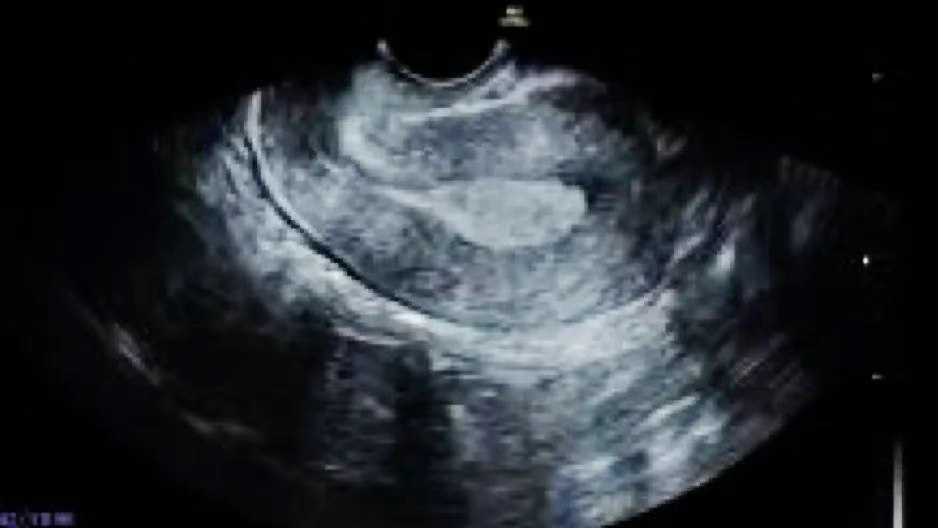

常见于月经第11-14天(接近于排卵期时或排卵后不久),内膜厚度约为9-12mm,超声下的表现为回声均匀但三线模糊。

常见于月经第15-28天(黄体期),内膜厚度约10-14mm,超声下的表现为无三线征。